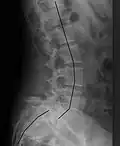

| X-ray of the lateral lumbar spine with a grade III anterolisthesis at the L5-S1 level | |

Spondylolisthesis is graded based upon the degree of slippage of one vertebral body relative to the subsequent adjacent vertebral body.[6] Spondylolisthesis is classified as one of the six major etiologies: degenerative, traumatic, dysplastic, isthmic, pathologic, or post-surgical.[7] Spondylolisthesis most commonly occurs in the lumbar spine, primarily at the L5-S1 level, with the L5 vertebral body anteriorly translating over the S1 vertebral body.[7]

Classification by degree of the slippage, as measured as percentage of the width of the vertebral body:[17] Grade I spondylolisthesis accounts for approximately 75% of all cases.[7]

- Grade III: 50–75%